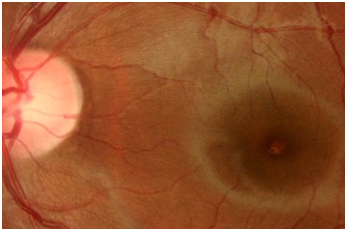

Figure 2 Left fundus photograph showing retinal pigment epithelial changes.

Fundus examination revealed retinal pigment epithelial changes on the fovea confirmed by OCT scan which is corresponding with the central scotoma on Amsler grid monitoring. Follow-up examinations revealed reduction in the area of RPE (retinal pigment epithelial hypertrophy) with no or little improvement of visual acuity measured by standardized Snellen or log MAR equivalent. There was no improvement in the area of central scotoma. The mystery remained on the power or class of laser pointer used. The RPE hypertrophy did not warrant any treatment as there was minimal evidence of inflammation and or fluid on the OCT scan. The RPE changes explained the area of scotoma and resolution in the thickness mapping of the subfoveal changes. After follow up of three months the patient who was a Turkish immigrant was lost to follow up (Figure 1–4).